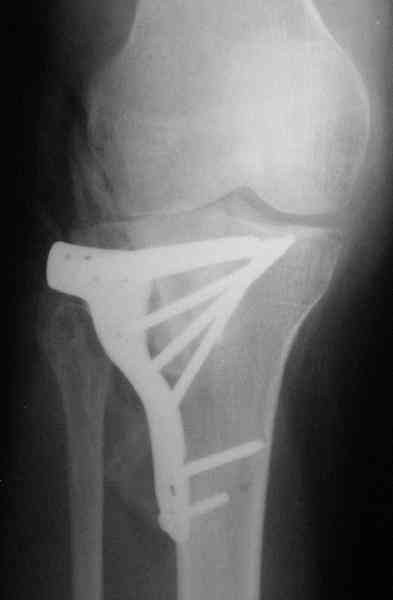

Наш план; доступ как подсказал Michael, по возможности репозиция, костная аутопластика дефекта метафиза, винты и спицы, АВФ и умеренная дистракция с шарнирными стержнями, и ранная пассивная разработка. Операцию планируем на следуюшей недели.

Уважаемый Абдурашид. Если нет противопоказаний , то из оперативных способов, я бы рекомендовал следующие: Полное замещение наружного мыщелка аллотрансплантатом либо открытая репозиция с элевацией и замещение дефекта ауто или аллокостью. В Ваших условиях , я бы рекомендовал второй способ. Во-время элевации необходимо разъединить фрагменты со стороны сустава ( надсечь скальпелем по линиям перелома, а затем тонким остеотомом их разъединить. При помощи долота произвести неполную остеотомию ( захватите не менее 1,5 - 2 см губчатой кости и поднять фрагменты, визуально отрепонировать и фиксировать 2-3 спицами. Дефект заместить костным ауто или аллатрансплантатом. Окончательная стабилизация пластиной ( лучше с угловой стабильностью, либо АВФ - позволит спокойно устранить угловую деформацию.

Через 3 месяца после перелома все еще можно выделить отломки, очистить от костной мозоли и и восстановить анатомию суставной поверхности. Фиксировать компрессионными шурупами. Важно помнить, что наружный мыщелок должен быть на 4-5 мм выше внутреннего. Передняя крестообразная связка обычно остается с частью кости и важно фиксировать ее проволокой по Ли. После восстановления суставной поверхности весь комплекс суставной поверхности нужно фиксировать к диафизу, можно использовать пластинку с фиксированными шурупами с наружной поверхности или две обычные с двух сторон или аппарат Илизарова. Важно сохранить задний наклон плато приблизительно 7 градусов. При закрытии доступа бугристость б.б кости фиксировать двумя шурупами. Важно добиться стабильности для максимально ранней разработки. Операция сложная, но интересная.